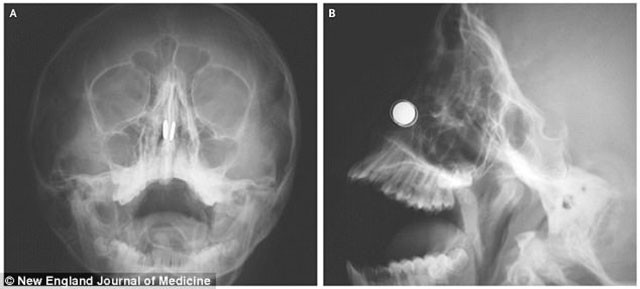

New England Journal of Medicine'de yazılan raporda doktorlar bu bölgeye sıkışan her türlü yabancı maddenin acil operasyonla alınması gerektiği konusunda uyardı:

: "Yabancı maddeler mukozaya baskı yaparak kangrene veya septal delinmeye neden olabilir."

Acil bir müdahaleyle mıknatısları çıkarmaya çalışan doktorlar da ilk denemede başarısız olduktan sonra burnun iki yanına başka mıknatıslar yerleştirerek çıkarmayı başardı.